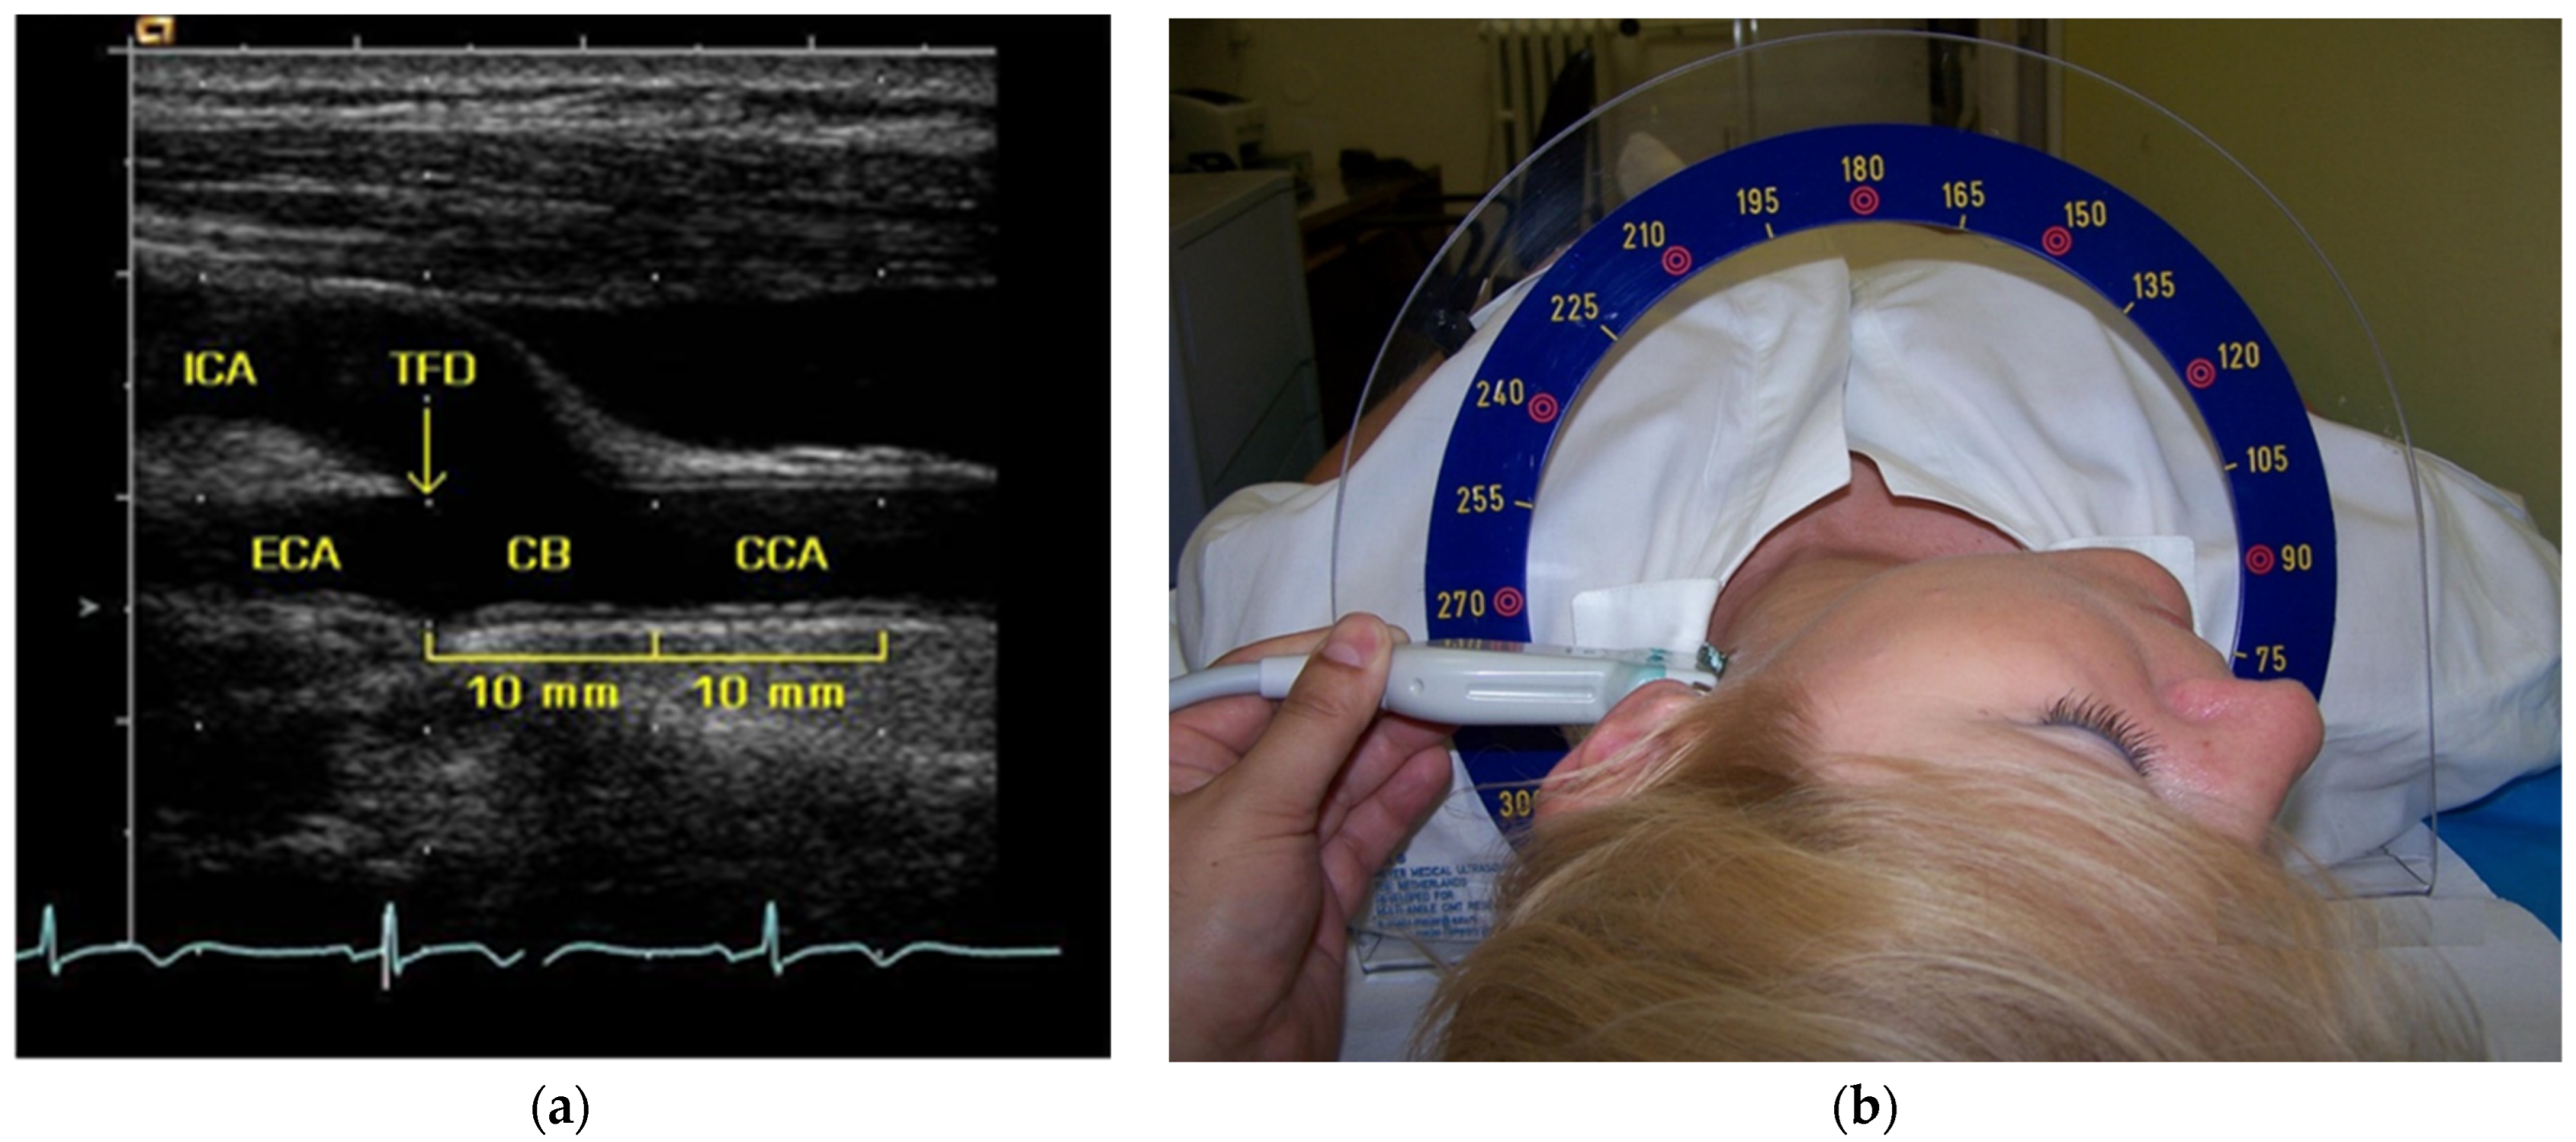

2.4. Carotid Ultrasound and IMT Measurement